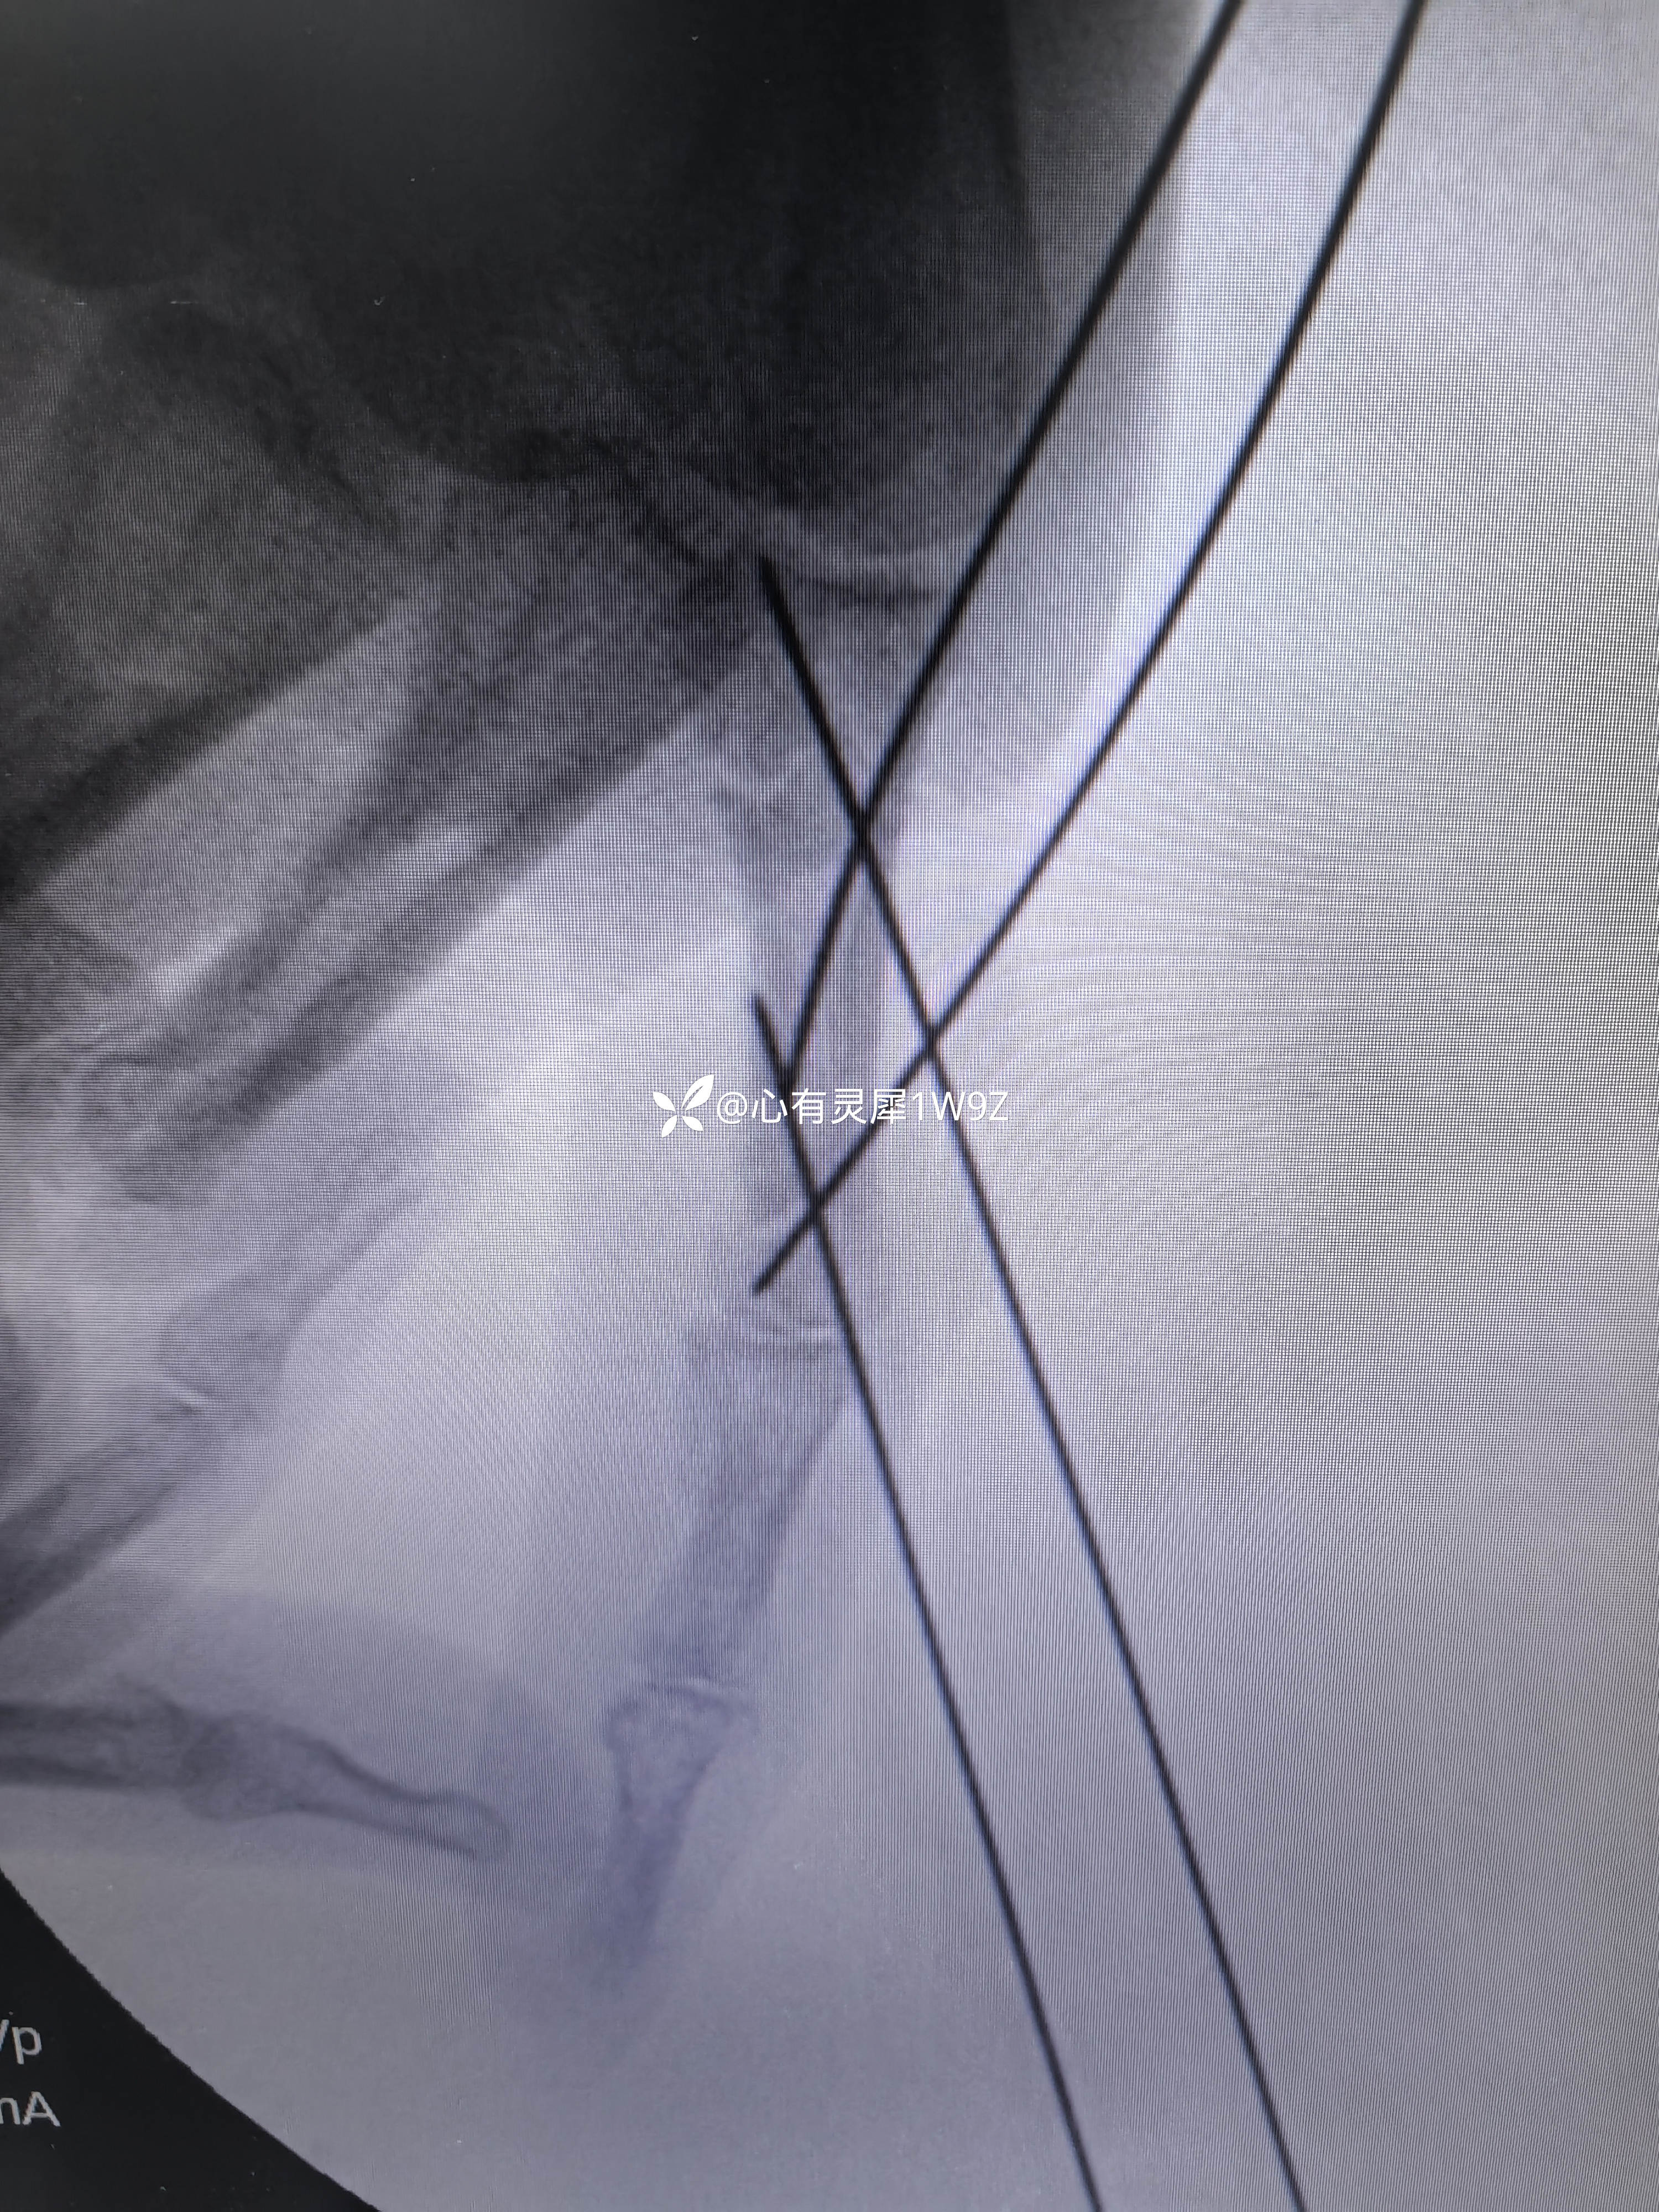

小指近节指骨两处骨折

【治疗经过及结果】: